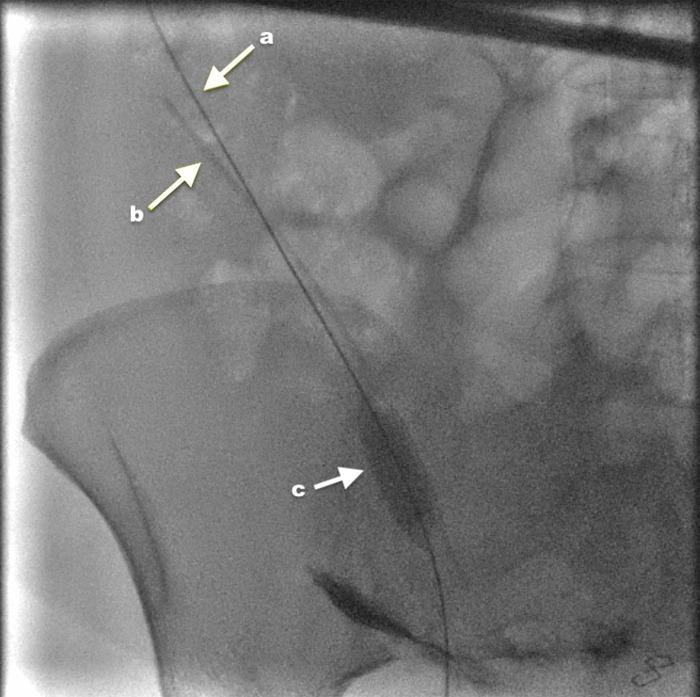

Iatrogenic retention of surgical drains following drain entrapment and breakage is a never event and a preventable complication. The traditional approach for removing a fractured drain from the intra-peritoneal cavity involves exploratory laparotomy. However, over the last few decades, minimal access surgery has been a more popular retrieval method for retained surgical items from peritoneal and extraperitoneal cavities. We report a case of a 32-year-old woman with a fractured pelvic drain post-caesarean section. Postoperatively, the patient developed the signs of infection and features of bowel obstruction. The mechanical obstruction was ruled out by computed tomography scan. Multiple attempts were made to pull the pelvic drain out but the tube snapped, leaving about a quarter of its length. The drain remnant was retrieved using a non-invasive, inexpensive interventional radiology technique. We could not find any such report in the literature describing this innovative approach for retrieving a fractured pelvic drain.

标题:经皮介入技术成功取出断裂盆腔引流管残段